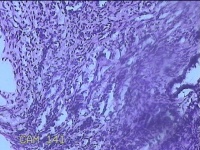

性别

女

年龄

28岁

临床诊断

子宫颈上皮瘤样病变

标本名称

宫颈9点组织

大体所见

灰白暗红色组织0.3x0.2x0.1cm两块。

图2